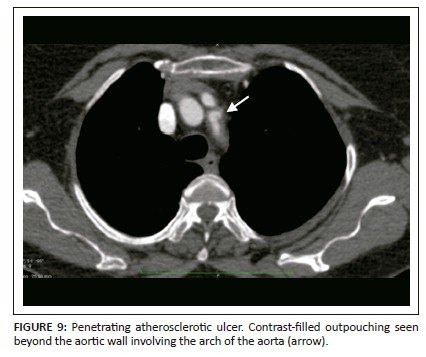

Extensive intimal calcifications are the frequent finding on unenhanced CT. A contrast-filled outpouching extending beyond the aortic wall is diagnostic of PAU (Figure 9). Hyperdense haematoma adjacent to the ulceration may be seen on unenhanced CT.14 The lesions can be single or multiple. Adjacent aortic wall thickening with atheromatous plaques are often seen. Penetrating atherosclerotic ulcer can progress to form a saccular aneurysm or even rarely, rupture. Additional imaging findings like haemothorax, haemopericardium, mediastinal haematoma, AD and ischemic findings owing to vascular obstructions can be seen as complications of PAU (Figure 10).